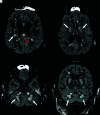

Diffuse ischemic lesions on FLAIR imaging. Axial (A–C) and coronal (D) FLAIR images show hyperintense ischemic lesions within the periventricular white matter, basal ganglia, cerebellar peduncles (white arrows), and the corpus callosum (A, red arrow).

Fig 5.